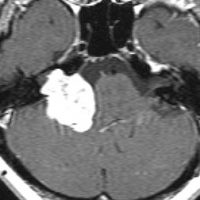

何も考えないで手術しなければならない時

聴神経腫瘍でまず手術が必要なのは巨大なものです。この4枚の写真は私が実際に手術をした患者さんのものです。脳幹部という脳の最も大切なところが腫瘍によって圧迫されて変形しているのが特徴です。右上のものはのう胞性腫瘍なので大きさの割に手術のリスクは高くありませんが,左上のものは実質性で出血性のものですごくリスクが高い手術でした。左下のものは普通のリスク。右下のものは超高難易度のものです。